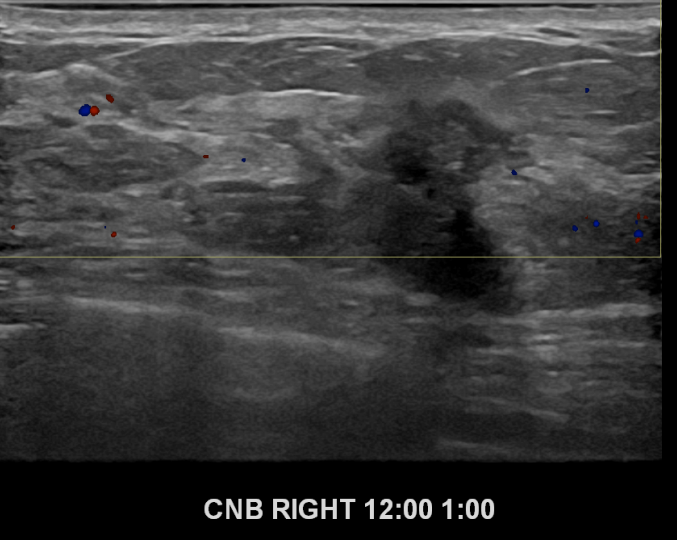

아산유외과개원후 691번째 유방암진단

상기환자 좌측유방에 딱딱한 멍울이만져져 내원하신 40대여성분으로 좌측유방의 혹 조직검사시행후 유방암 진단되었습니다